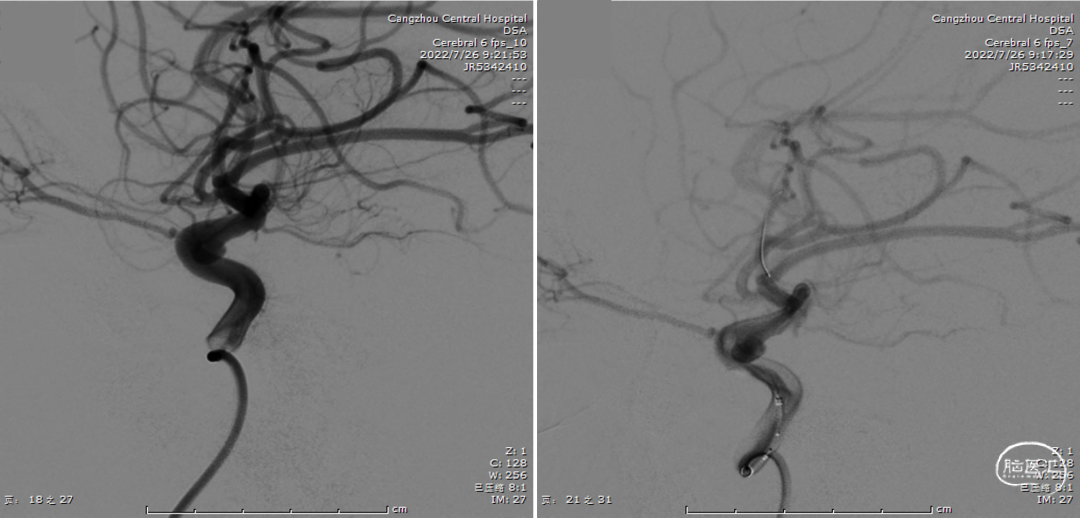

全脑血管造影(2022年7月26日)

术中定位图像

Xper CT HiRes Cran.Stent